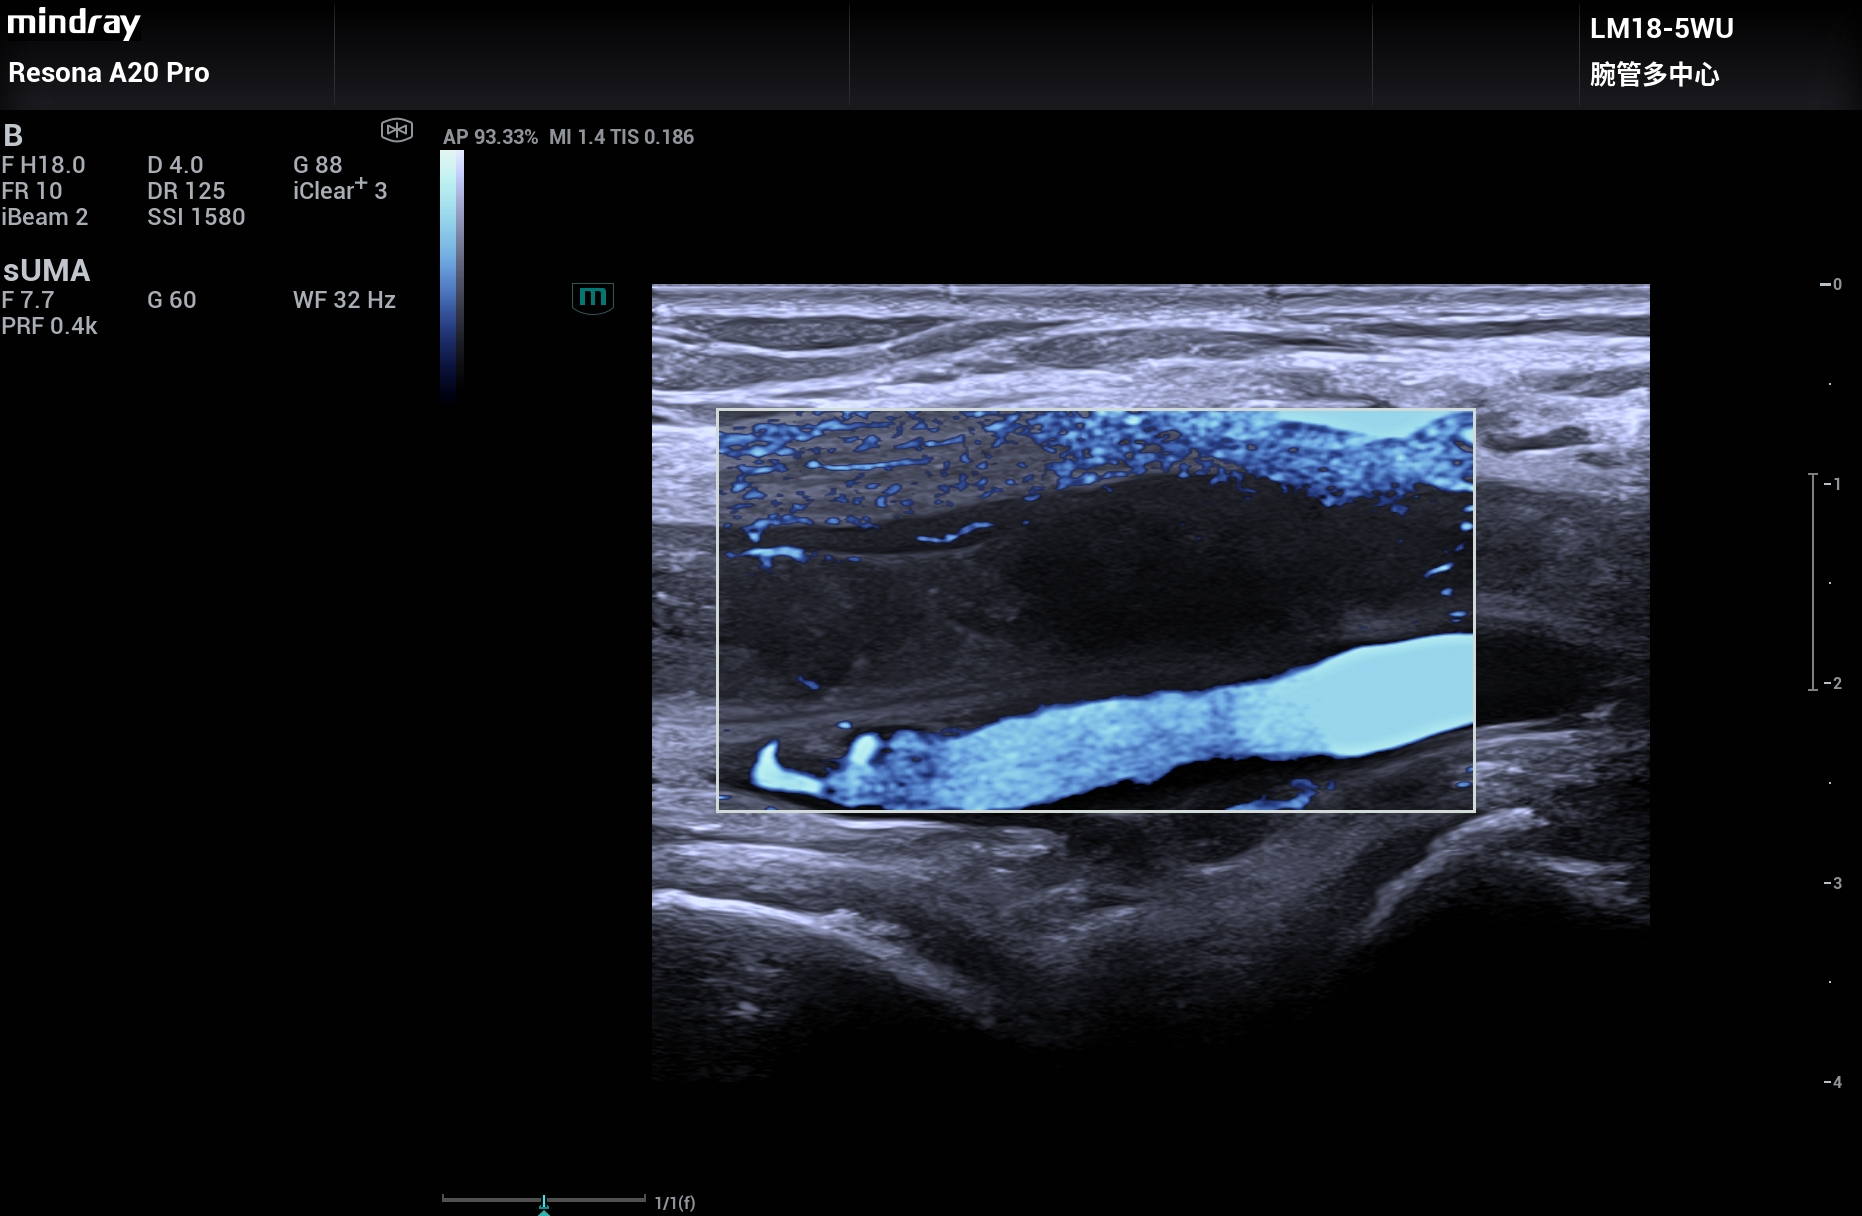

下肢深静脉血栓,超微血流能显示血栓内的微小血流,大大提高确诊的信心,Resona A20。